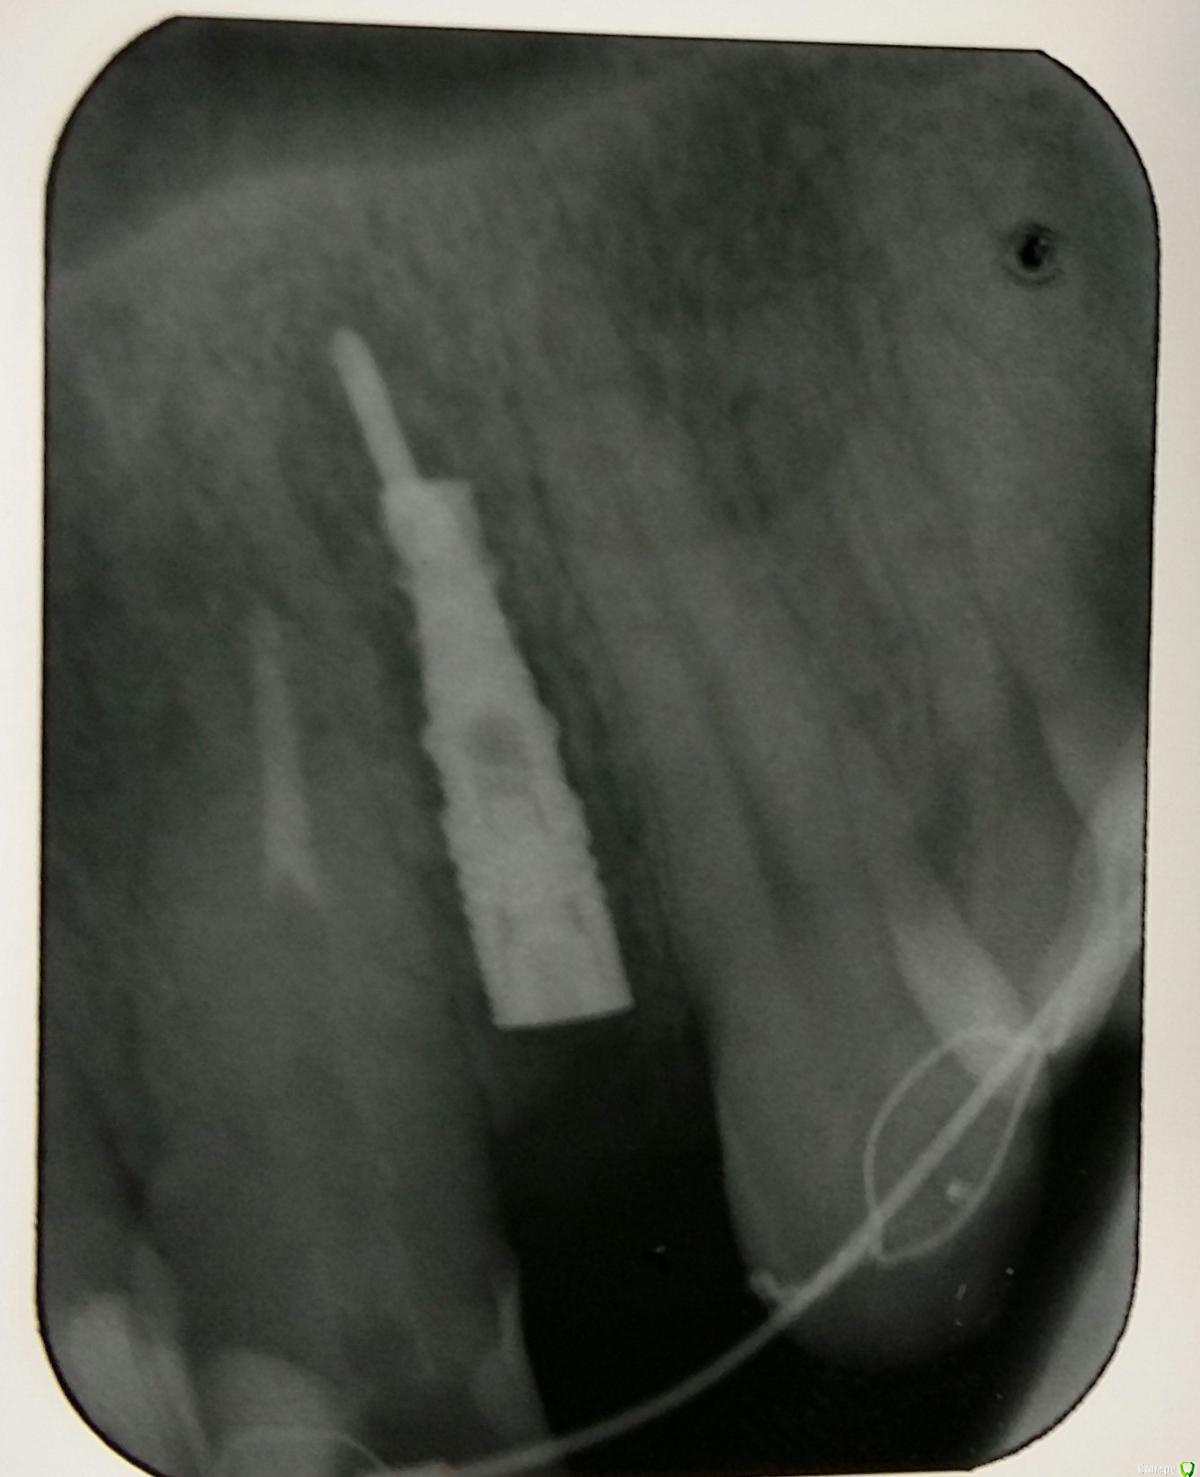

Kostoprav Опубликовано 8 июля, 2015 Поделиться Опубликовано 8 июля, 2015 ИЗНАЧАЛЬНАЯ СИТУАЦИЯ ПОЛУЧИЛОСЬ сори что нет фото до имплантации. Блок взял с тела челюсти, фиксировал двумя винтами (во время имплантации выкрутил только один), присыпал gen os, укрыл дермой-получил заметный прирост слизистой) имплант альфадент 3,75х11,5 2 Ссылка на комментарий

Mane Опубликовано 8 июля, 2015 Поделиться Опубликовано 8 июля, 2015 (изменено) Видно что блок прирос. Здорово Остальное оценить сложноМне нравится положение импланта в плане оси. Но уровень заглубления не ясенТакже не видно прироста десныВ общем мало данных для оценкиНо опять же вам именно она и нужна? Изменено 8 июля, 2015 пользователем Mane Ссылка на комментарий

Kostoprav Опубликовано 8 июля, 2015 Автор Поделиться Опубликовано 8 июля, 2015 Видно что блок прирос. ЗдоровоОстальное оценить сложноМне нравится положение импланта в плане оси.Но уровень заглубления не ясенТакже не видно прироста десныВ общем мало данных для оценкиНо опять же вам именно она и нужна?по вестибюлярной поверхности заглубил приблизительно на 1мм с небной больше получилось. слизистая по сравнению с первым разом значительно толще стала, доказать к сожалению не могу так как не делал фото(: я выложил этот пост не только ради оценки, может кому из начинающих данный случай сгодиться 3 Ссылка на комментарий

Kostoprav Опубликовано 28 июля, 2015 Автор Поделиться Опубликовано 28 июля, 2015 Сколько времени прошло после фиксации блока? Чем забирает е блок? на момент имплантации 6 мес. забор блока делал линденманом Ссылка на комментарий